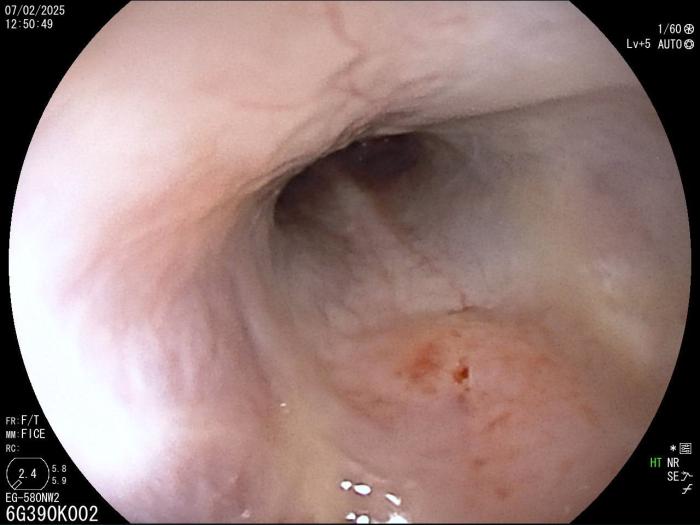

Rinoscopia anterógrada y retrógrada (día 6), con acceso a través de los ollares (acceso retrógrado) y a través de cavidad oral y nasofaringe (acceso anterógrado) con obtención de moco profundo para su cultivo bacteriano, sin observarse anomalías morfológicas (Figura 2), y otoscopia con miringotomía para el drenaje de contenido purulento y toma de muestra para cultivo bacteriano. Las muestras se envían al laboratorio de referencia.

Rinoscopia anterógrada y retrógrada (día 25): se realiza ante la persistencia de secreción nasal bilateral tras antibioterapia, observándose eritema y secreción mucopurulenta y la presencia de un pólipo nasal en la cavidad nasal izquierda (Figura 5A-B), cuyo estudio histopatológico revela una lesión de tipo inflamatorio linfoplasmocitario. La fístula oronasal se ha resuelto completamente. Se observan lesiones líticas en cornetes nasales y endoturbinados.